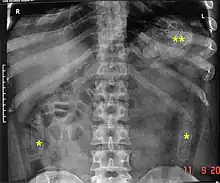

Plain radiograph of the abdomen of a drug "mule" showing drug capsules

Abdominal X-ray showing swallowed packages of cocaine.

Routine detection of the smuggled packets is extremely difficult, and many cases come to light because a packet has ruptured or because of intestinal obstruction. Unruptured packets may sometimes be detected by rectal or vaginal examination, but the only reliable way is by X-ray of the abdomen. Hashish appears denser than stool, cocaine is approximately the same density as stool, while heroin looks like air.[11][12]